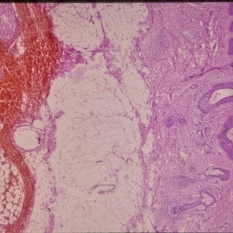

Histopathology of Linear Sebaceous Nevus Syndrome

Histopathology of Linear Sebaceous Nevus Syndrome

Feb 20 2015 by H. Michael Lambert, MD

Histopathology of linear sebaceous nevus syndrome.

Condition/keywords: histopathology, linear nevus sebaceous syndrome